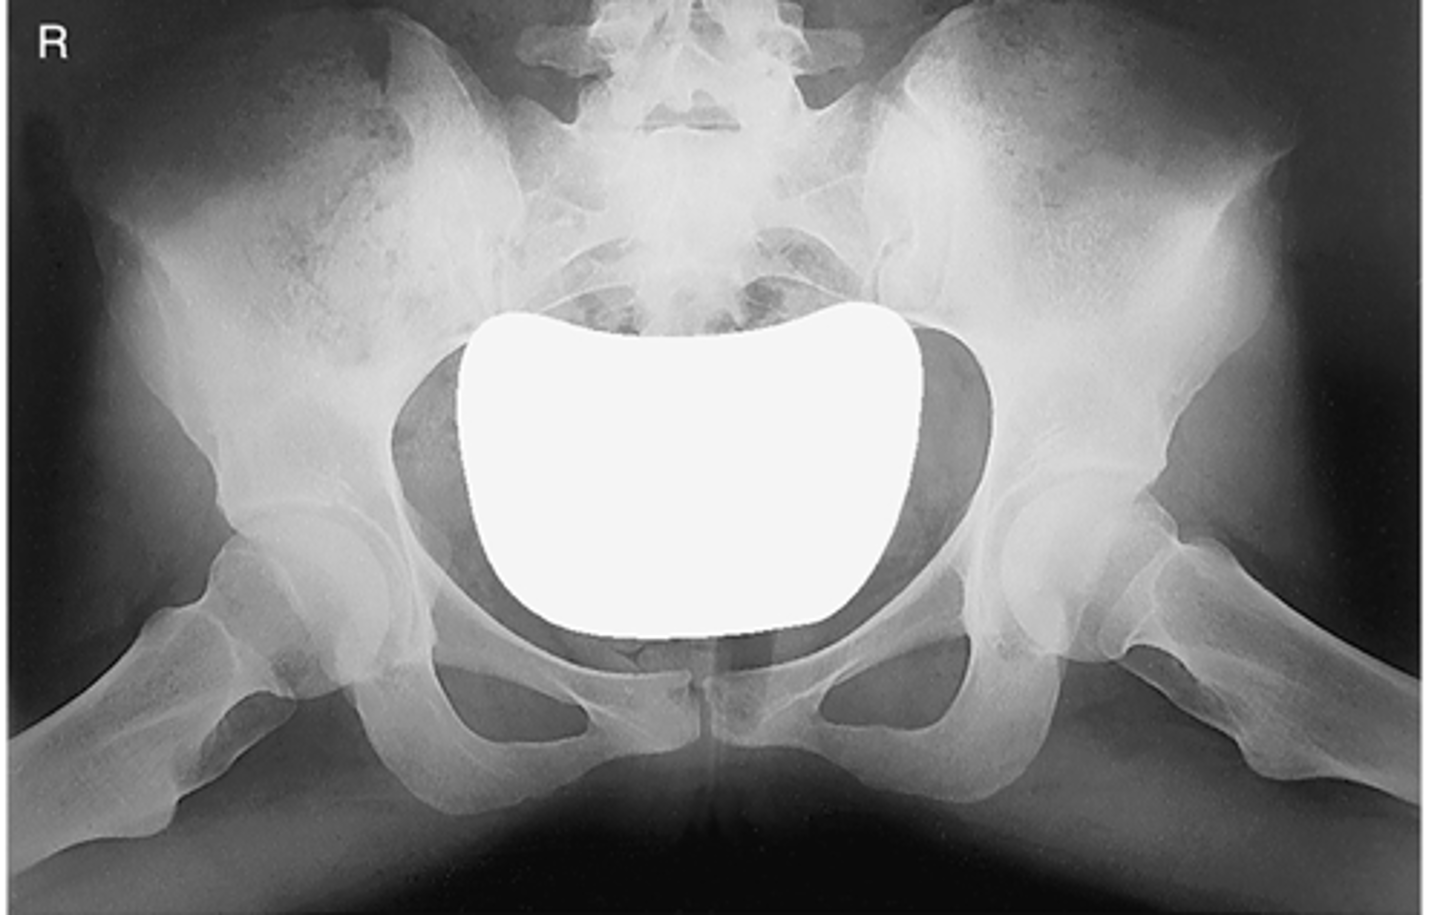

AP pelvis

ID standard bilateral pelvis projection

<p>ID standard bilateral pelvis projection</p>